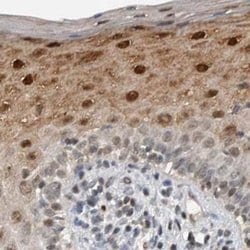

Invitrogen™ ZNF521 Polyclonal Antibody

Brand: Invitrogen™ PA554898

| Immunohistochemistry (Paraffin) | |

| Recombinant protein corresponding to Human ZNF521. Recombinant protein control fragment (Product #RP-93654). | |